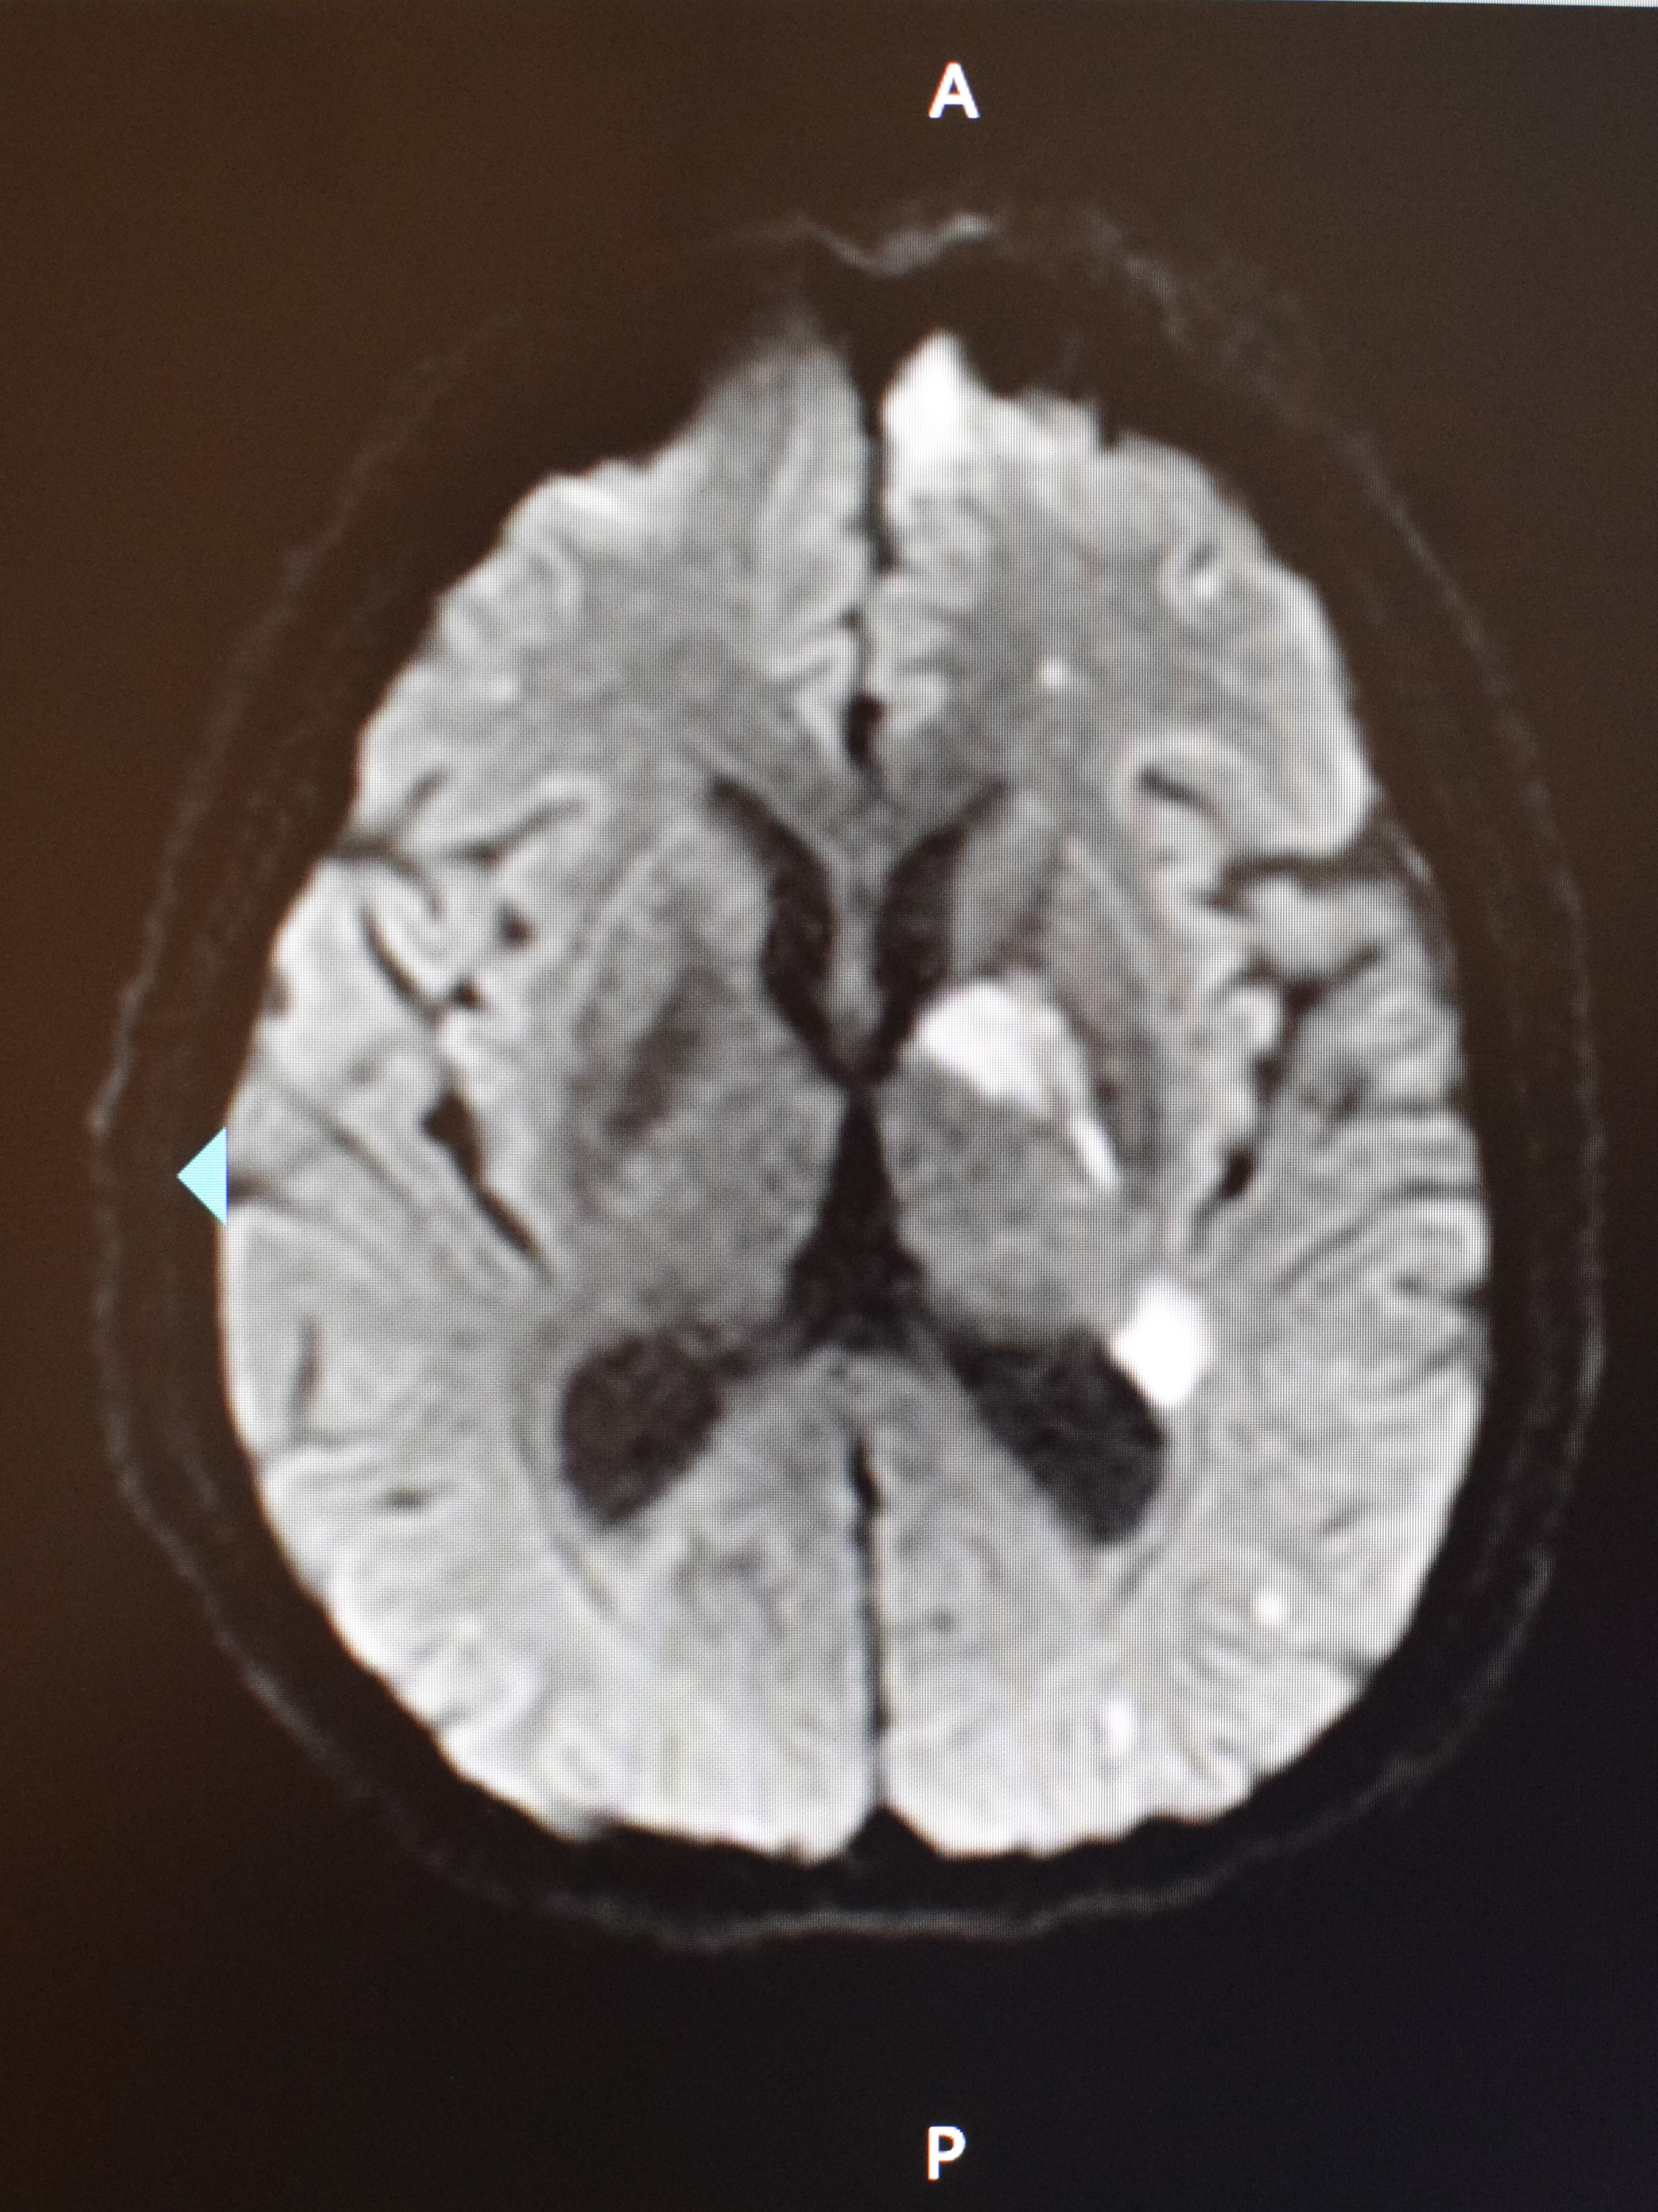

8月25日行鼻内镜下左侧鼻腔、鼻窦、颅底感染清创术与左侧眶内侧壁、眶底壁减压术。术中见左侧鼻腔外侧壁、下鼻甲、鼻顶、鼻中隔黏膜大面积坏死、结痂,左侧鼻泪管、眶筋膜以及面部软组织受累,眶内脂肪组织水肿。术中冷冻快速病理:送检组织慢性炎,另见炎性坏死组织,其内查见真菌菌团,考虑毛霉菌感染(见图 3)。术后第1天发热,体温最高38.0 ℃,给予口服泊沙康唑、头孢曲松,胰岛素控制血糖等治疗。G试验和GM试验阴性,鼻拭子细菌培养阴性。患者于8月28日20:00出现言语混乱、右侧肢体肌力降低,MRI示左侧大脑半球、基底节区多发急性梗死(见图 4),皮下注射依诺肝素钠注射液40 mg每12 h一次抗凝、口服阿司匹林100 mg 3次/d抗血小板、扩血管等治疗。患者眶蜂窝织炎,请眼科会诊,建议继续抗感染治疗、处理脑梗死,待病情平稳后处理眼部病变。经过抗感染治疗,患者仍反复发热,结合患者嗜睡等,考虑可能合并颅内感染,将抗生素升级为美罗培南。于8月30日回当地医院继续治疗。

| 患者颅脑MRI(DWI)示左侧大脑半球、基底节区多发急性梗死 图 4 患者8月28日颅脑MRI(DWI) |